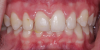

(10.) Retracted posttreatment view of the crowns after they were stained and glazed and placed with resin cement.

Figure 10